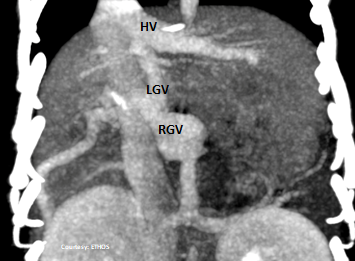

Does the Shunt enter the Phrenic vein or the Left Hepatic Vein?

Does the RIGHT GASTRIC VEIN (RGV) contribute blood to the shunt?